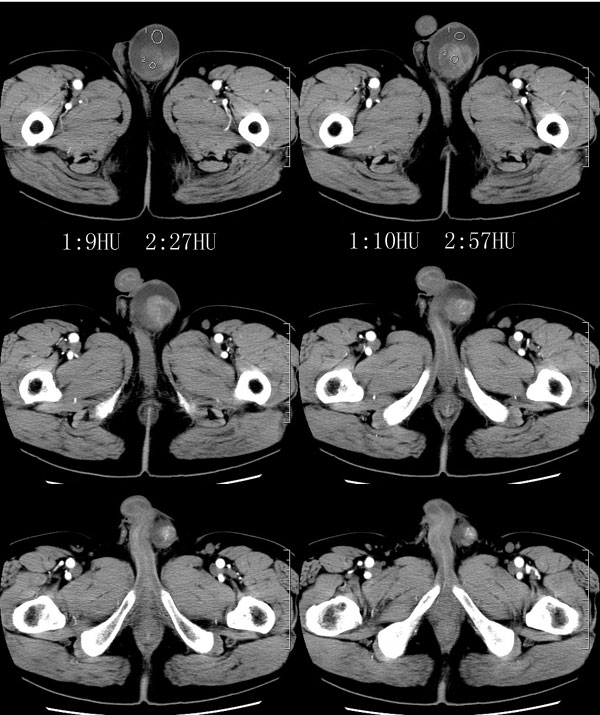

| 男性,69岁。自2个月前开始无意中发现左侧阴囊内一鸡蛋大小肿物,当时无伴疼痛等不适,未予重视。肿物逐渐增大,近段时间常伴左会阴部、腹股沟区牵扯不适,并于2周前在我院门诊行彩超检查提示“左侧附睾肿瘤可能,左侧睾丸鞘膜积液”。 专科检查:左侧阴囊肿大,其内可触及一鹅蛋大小肿物,表面光滑。肿物前部呈囊性感,后部质硬,按压无疼痛,无缩小,活动度良好。左侧睾丸未触及,透光试验(±)。                 王仕学发言:左侧睾丸见一密度不均肿块,边缘清楚,周围见水样密度影;考虑睾丸生殖细胞性肿瘤可能性大. 睾丸肿瘤占生殖系统肿瘤的3%-5%,占男性恶性肿瘤的0.5%-1.0%,其中生殖细胞性肿瘤占95%.睾丸肿瘤包括生殖细胞和非生殖细胞肿瘤两大类,前者占95%以上,后者不到5%.非生殖细胞肿瘤虽少见,但种类繁杂,主要有支持细胞、间质细胞和支持细胞-间质细胞瘤等功能性肿瘤,和间皮瘤、腺癌、横纹肌肉瘤、粘液性囊腺瘤、纤维上皮瘤、黑素神经外胚瘤、淋巴瘤等附属组织肿瘤。不同的病理类型的睾丸肿瘤发病率高峰不同,睾丸癌多发于35岁以前,精原细胞瘤发病高峰为30-35岁。精原细胞瘤约占睾丸肿瘤的60%,发病高峰在30-35岁。85%的患者睾丸有明显肿大,肿瘤局部侵犯力较低,肿瘤一般有明显界限。 手术:行“左侧附睾、睾丸、精索切除术”。 病理诊断:(左睾丸、附睾)肿物,为低分化腺癌。另送检(左精索远端)肿物,镜下亦为低分化腺癌。 免疫组化:ck(l)(++++)、cea(+++)、ca19-9(-)、psa(-)、plap(-)、p53(-)、vimentin(-)。 原贴地址:http://www.radinet.com.cn/forum_view.asp?forum_id=4&view_id=30707 |